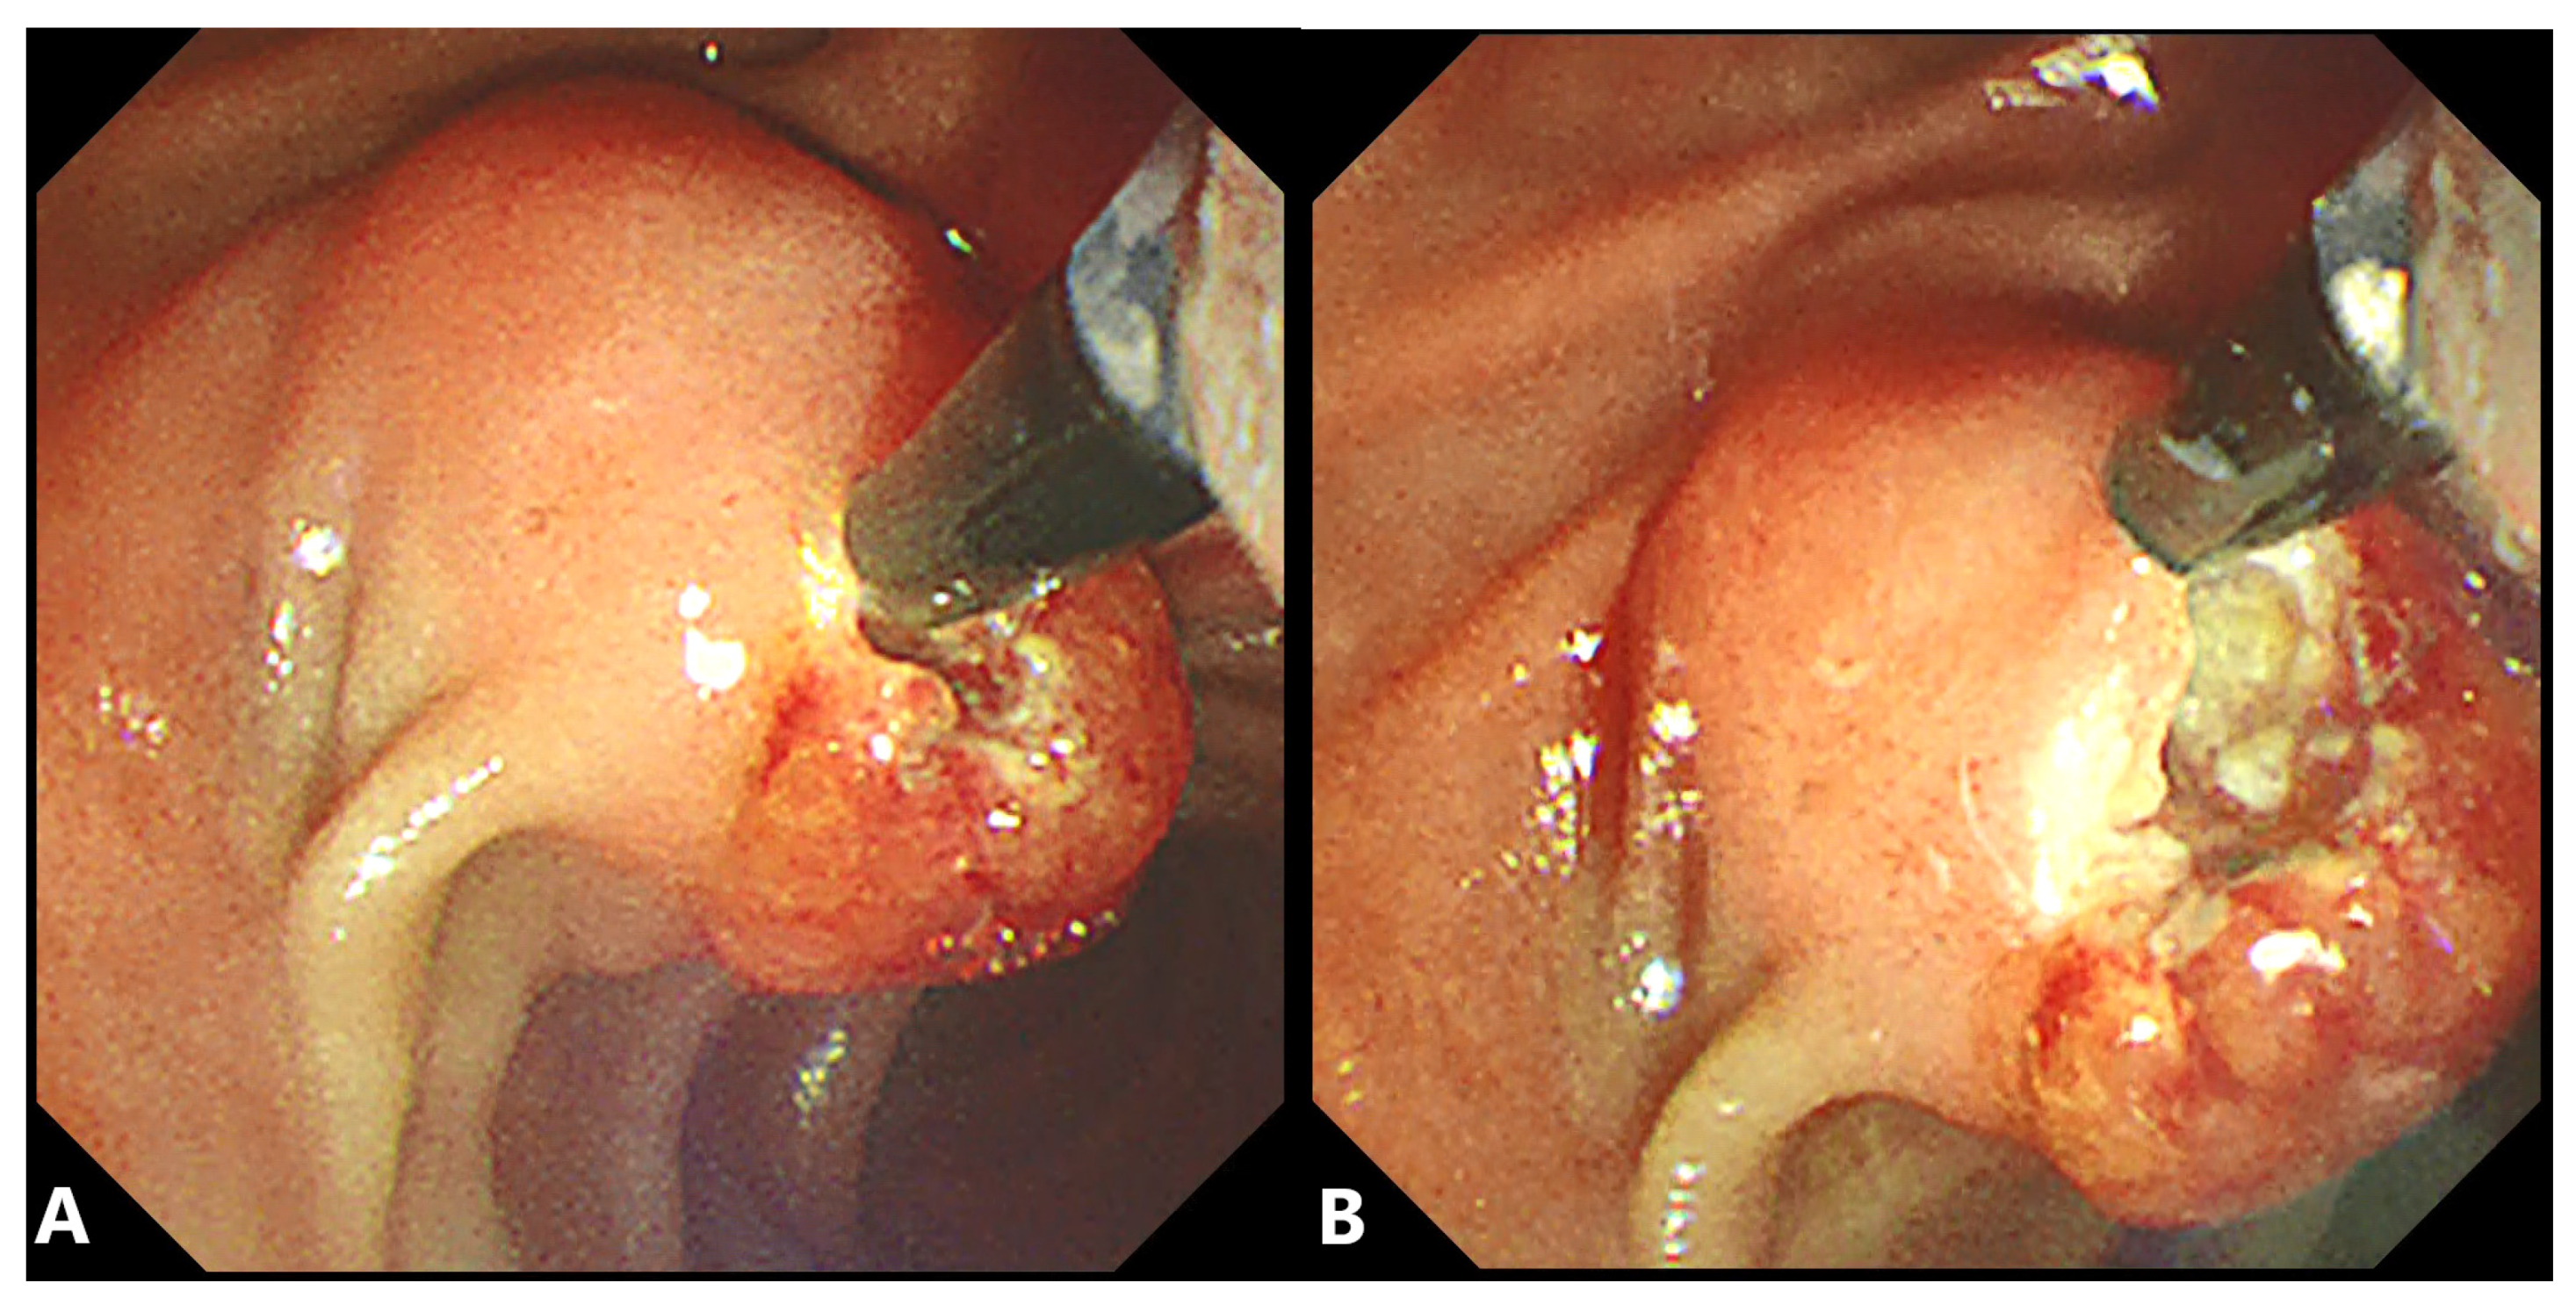

2.2. Precut Papillotomy